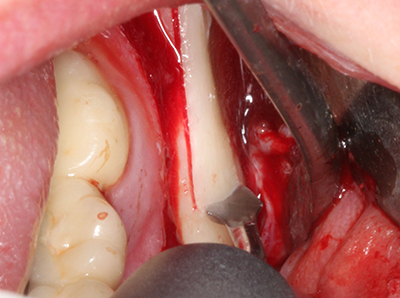

Когато се извършват хирургични процедури върху кост в непосредствена близост до чувствителни структури като кръвоносни съдове или нерви, ротиращите инструменти създават значителен риск за ятрогенно нараняване. Пиезоелектрическите апарати могат да бъдат от помощ при препарация на костно покритие и отстраняване на твърда кост близо до нерви, особено за оголване на нервите след ятрогенно нараняване, както и по време на латерализация на нервите за резекционни и реконструктивни процедури или поставяне на имплант (Фиг. 17-20). Лекият контакт между пиезонакрайника и нерва по принцип не води до нараняване, но ако действате непредпазливо с трионообразни движения или приставки за остатъчен костен субстрат, може да причините временно или перманентно увреждане на нерва. Въпреки това, рискът от увреждане се счита за много по-малък, отколкото при употреба на триони или ротиращи инструменти (Pereira, Gealh et al. 2014).